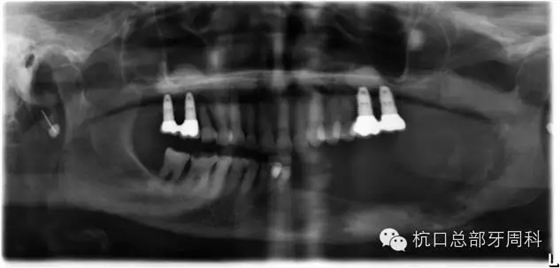

2012.4

2013.1

2013.3

下頜所有牙齒自動脫落,炎癥累及整個下頜骨,包括左側(cè)髁狀突,病理性骨折左側(cè)聽力喪失